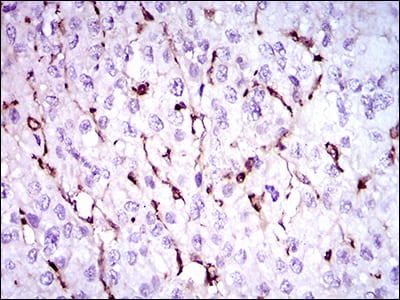

分类: 科研抗体货号: 30485P别名: GT; GTA; CD41; GP2B; HPA3; CD41B; GPIIb; BDPLT2应用: IHC,FCM反应种属: Human